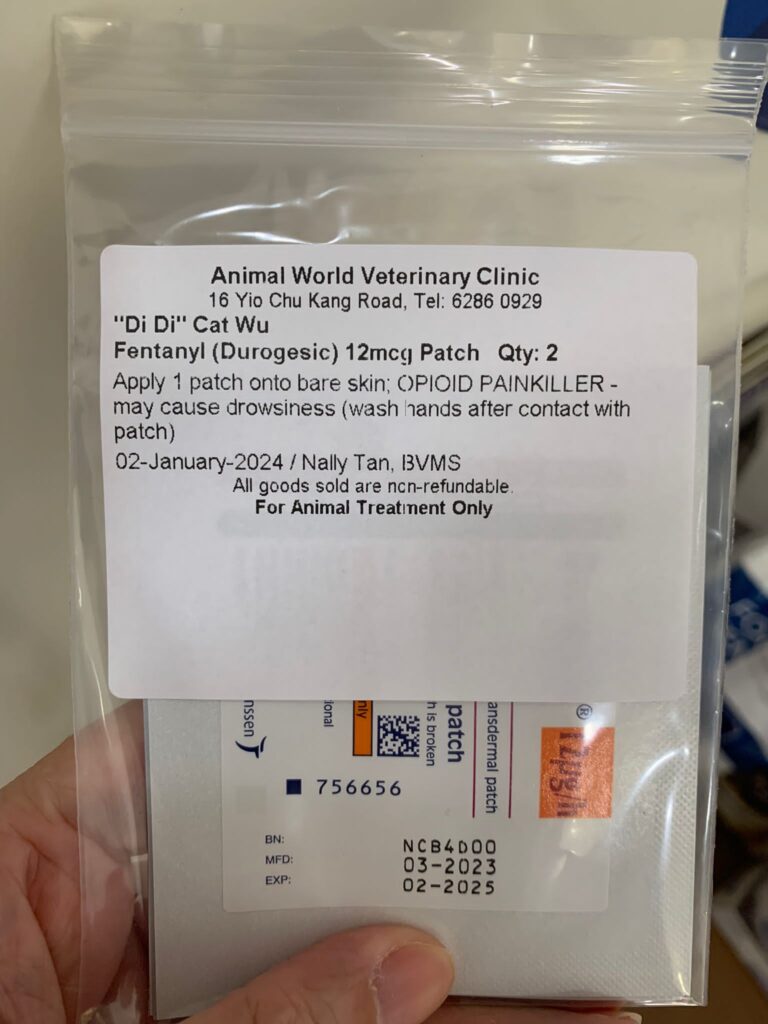

Night: Tmr got to put new f patch for him or give bupre alr

10am: eyes more discharge I assume is due to pain, today will shave his ear and put f patch and give bupre and Subcut

Night; did looks more in pain. Bupre in the day not enough. Have to put f patch

Morning: looks in pain. Give Subcut and bupre. I don’t have f patch in 5G. scanned on 19.4.24 no m/c.

Morning: got helper in to cut nails, steam bath and clean ears. She can handle him alone. Given Subcut bupre n put on f patch for him.

Morning: got 2 helpers in to clean up and for him: cut nails, clean ears and steam brush fur. His f patch if off, given Subcut and bupre jab

Morning; both eyes discharge look bad, clean up and put banocin on his ear. Will Subcut him and give Clav jab and bupre n put on new f patch for him

Morning: Subcut n on regular med and place new f patch n still given bupre

10am+: b4 I Subcut n give painkiller still eating ok. Subcut and given b12 b com bupre and put on a f patch (end 1.3.24)

11Am+: given bupre jab and place a f patch on his left ear.

Morning: his fentalyn is off. Given Subcut and bupre.

Morning: didi constipated, saw him in 2 bins, trying to squeeze out something n can’t n he try to rub on floor – aren’t that pushing that piece in? I help him push out the 2cm piece 5/10, and he go to bin 03 and poo out another 12cm. So is that piece stuck n he is so uncomfortable. Subcut him w bupre also. His f patch still on. Can tear off soon. Need to buy more

Morning: will meow. Like to eat Sanyo pink elderly food. His f patch still on it

Just status update: Today Subcut n given b12 b com also. Given bupre and fercosang also. eye more discharge. Pain. Shave his ear and place a f patch also.

Night; mmm”Don’t look good.”- pic is in pain. Tmr got to try a f patch on him again

His f patch is off alr

1+pm back to 猫房 w f patch. Clean his ears and only manage to cut off some of his ears fur w scissor. I don’t have shaver for 5G have to go buy. Sigh. Put a patch on his right ear. Still v responsive to me sayang and head butt

I need to measure his weight and change to higher dose for him. I think I need to put a f patch for him